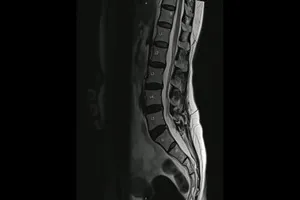

2. 척추 질환

· 허리 디스크, 목 디스크

척추뼈 사이의 디스크가 튀어나와 신경을 압박하는 질환으로, MRI 검사를 통해 디스크의 위치와 정도를 확인하고 치료 계획을 세웁니다.

· 척추 협착증

척추관이 좁아져 신경이 압박되는 질환으로, MRI 검사를 통해 협착된 부위를 확인하고 치료 방법을 결정합니다.